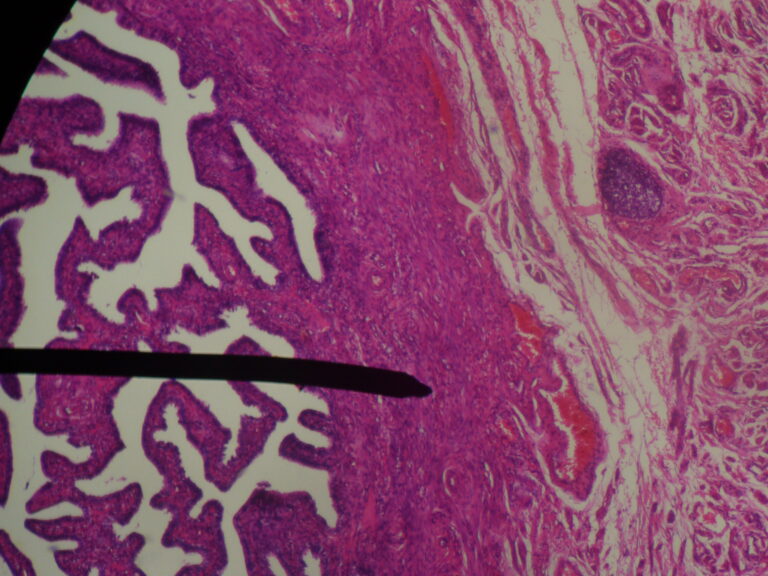

From www.pathologyoutlines.com

Pathology Outlines Anatomy, histology, embryology & features to report Bands On Fallopian Tubes Tuba uterina 8 ), also known as the uterine tube or, less commonly, the oviduct, is a paired. scar tissue may form and block the fallopian tubes. imaging evaluation of fallopian tubes and related disease: Abnormalities in the pelvis can block the tubes or prevent the egg from. the fallopian tube ( ta: adhesions are abnormal. Bands On Fallopian Tubes.